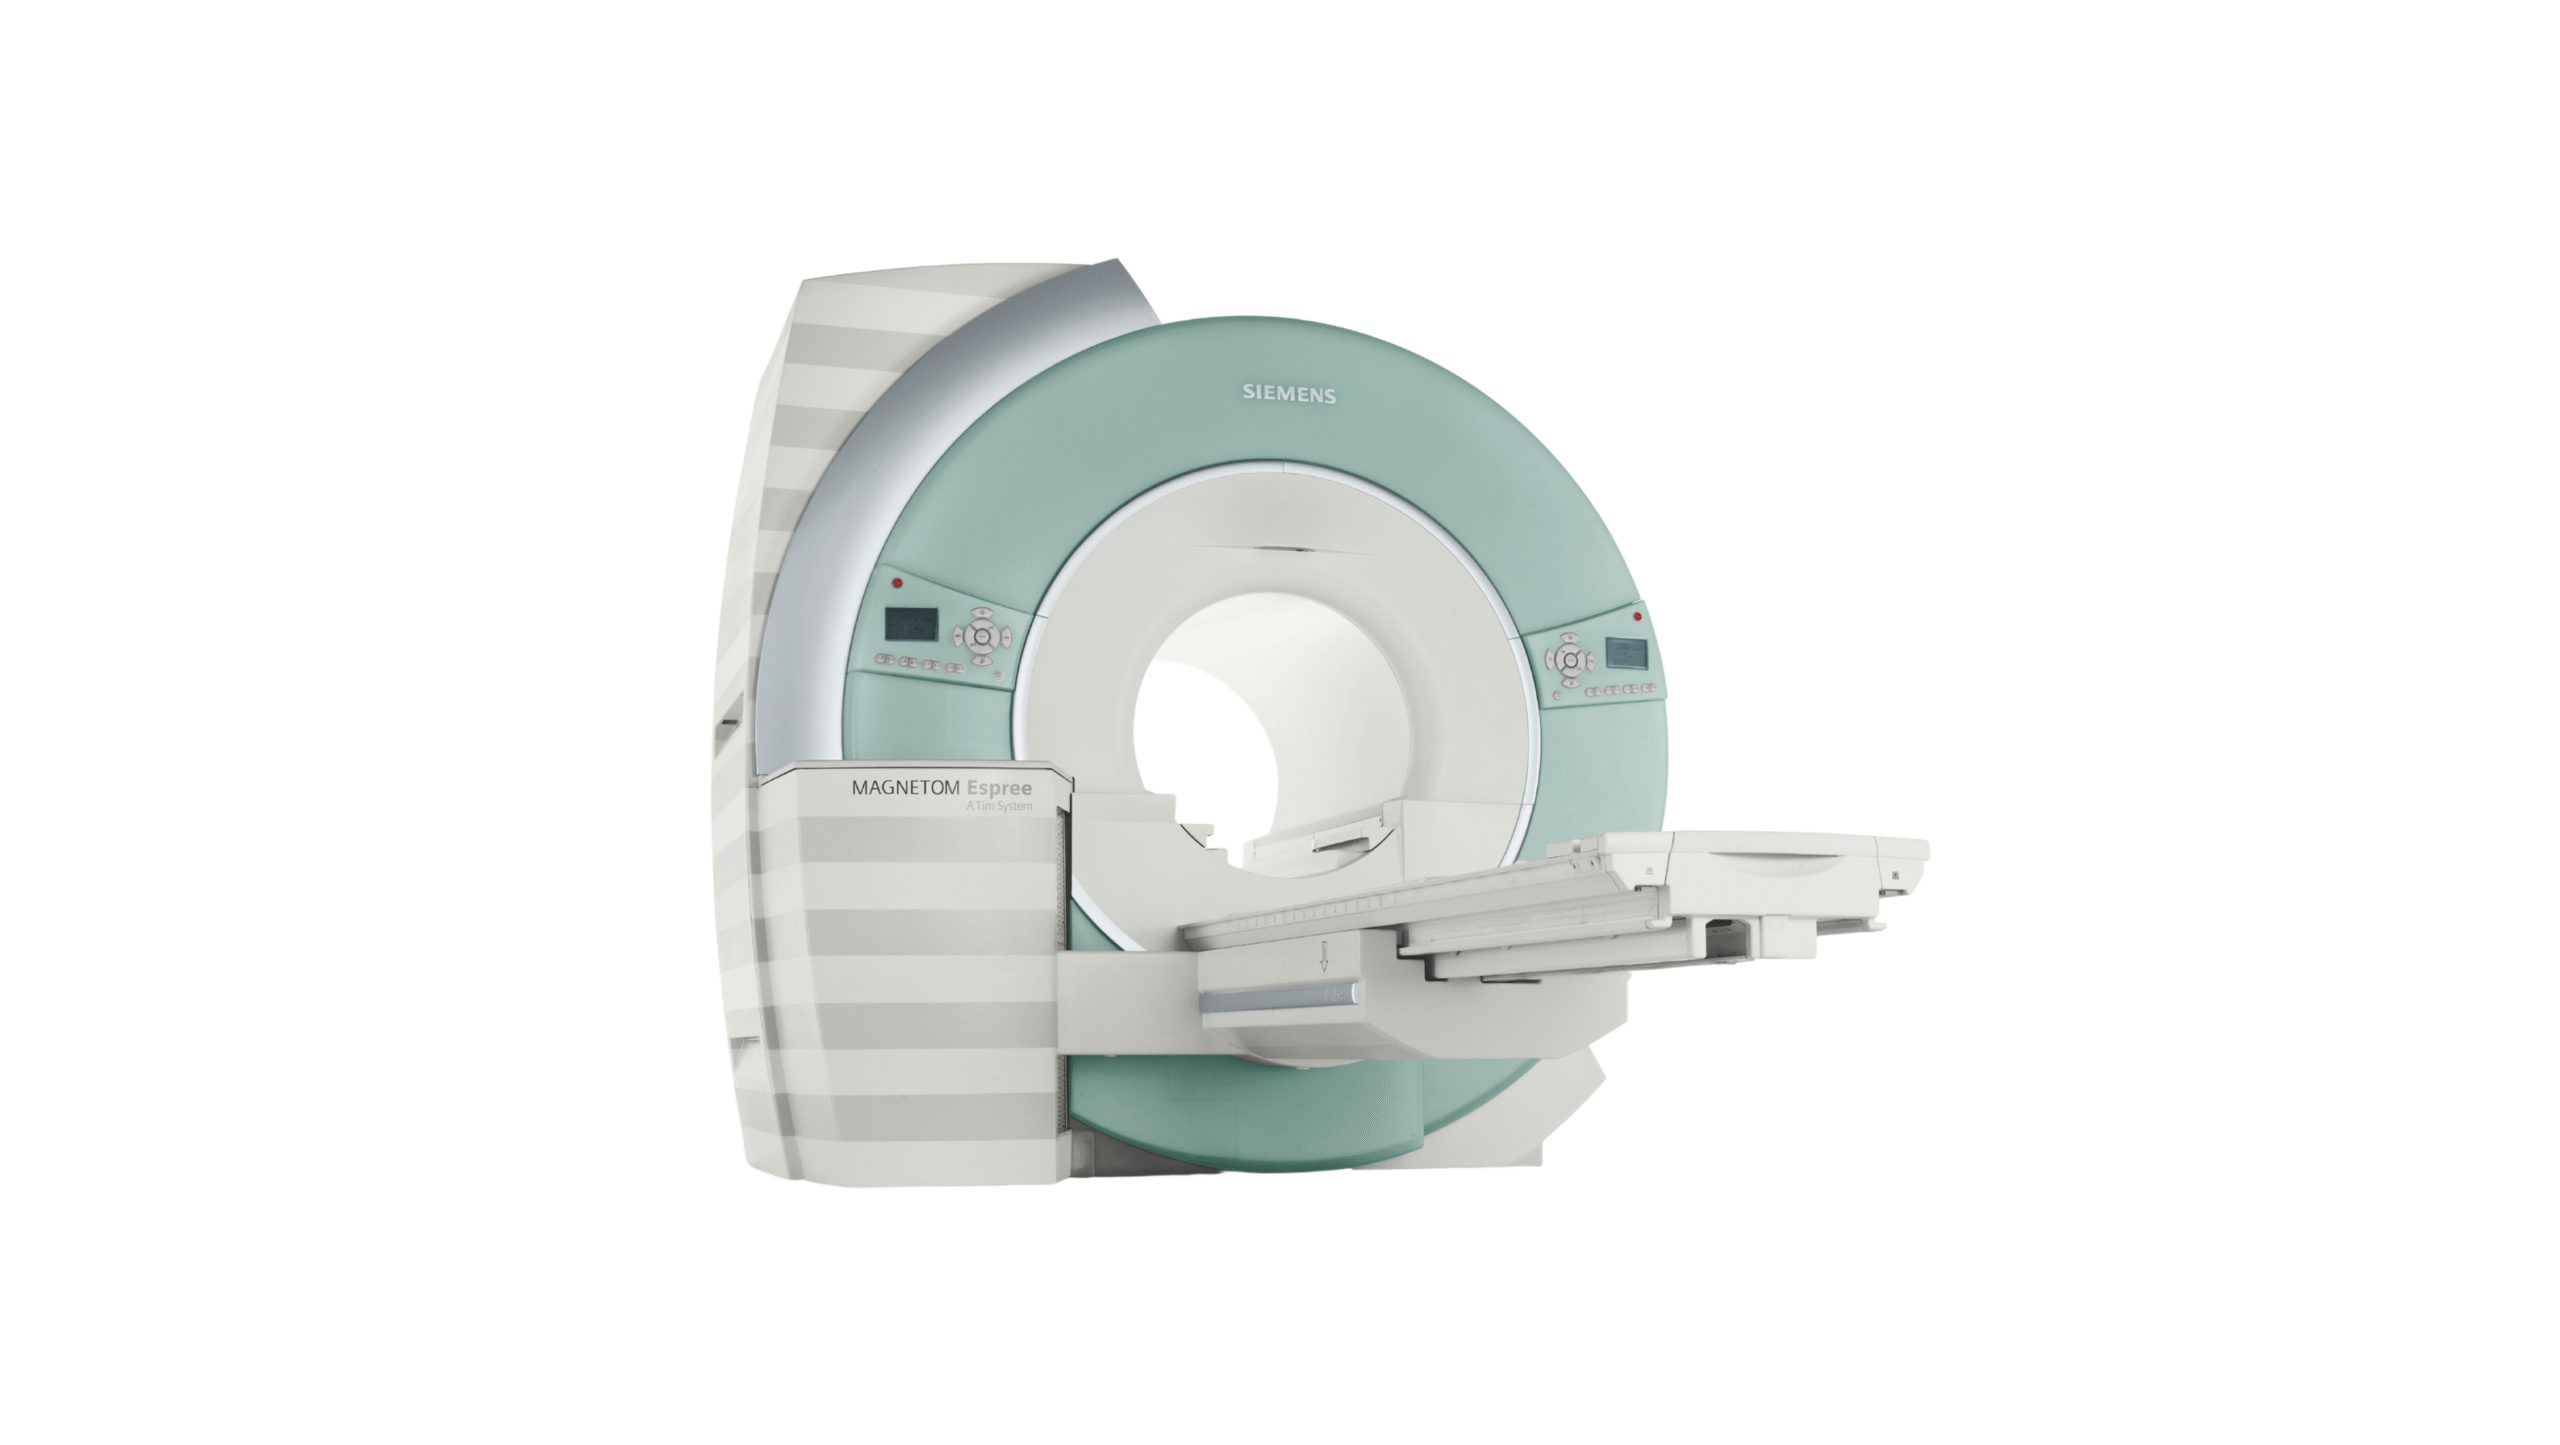

Medical equipment marketplace

Products

Medem ltd. is a global medical distributor of equipment and consumables.

We provide reliable service for our partners all around the globe. Offering well-known brands such as Fujifilm Healthcare, Carestream Health, Konica Minolta Healthcare and many others. Minimum order quantity is 1 pallet.